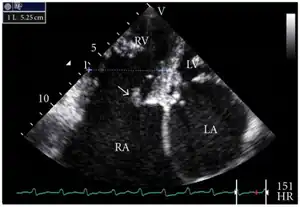

Diagram of the heart with a black arrow showing the location and direction of the abnormal blood flow